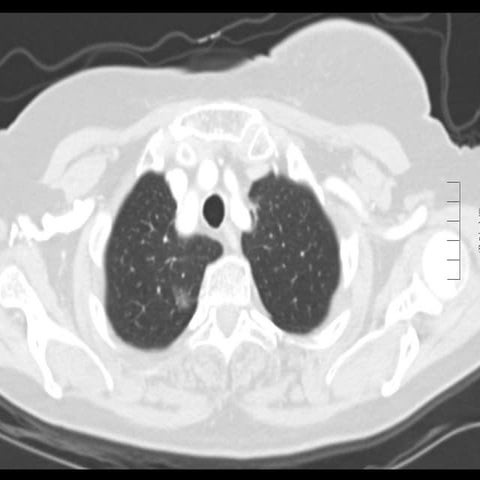

40 year old